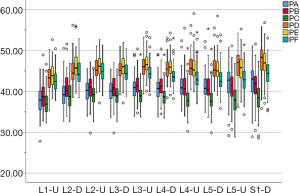

The lengths of each path (Table 1)

In the medium group, PC path was the shortest (38.56±3.25 mm), PA path and PB path had little difference (P=0.123), and there was no statistical significance. In the full-length group, PF path was the shortest (43.86±3.09 mm), and there was no significant difference between PD path and PE path (P=0.177) (Figure 10). All the paths increased successively from L1 to S1, among which PA and PD paths were the most obvious, followed by PB and PE paths. PC path and PF path first increased and then decreased (Figures 11,12).

The angles of each path (Table 2)

The included angles a1, a2, a3, b1, b2, b3 and c1, c2 and c3 in the sagittal plane were significantly different (P≤0.001) (Figure 13) (a1 > a2 > a3, b1 > b2 > b3, c1 < c2 < c3). In the angles of sagittal down-path, b1, b2 and b3 change significantly and consistently, showing a trend of decreasing first and then increasing, which is the smallest at L3 (46.08±4.37°, 36.21±3.51°, 22.47±3.01°) and the largest at S1 (69.49±8.28°, 61.23±7.74°, 36.60±5.00°). In the angles of sagittal up-path, a1 and a2 change in the same way, showing an increasing trend. While a3 goes down and then goes up, which is the smallest at L4 (23.43±4.29°) and the largest at L5 (24.36±2.94°). In the angles of axial plane, c1, c2 and c3 change in the same way, showing a trend of increasing first and then decreasing. c1 and c2 are the largest at L2 (40.07±2.75°, 55.1±3.32°), and c3 is the largest at L3 (73.11±2.10°). c1, c2 and c3 are the smallest at S1 (33.87±2.94°, 47.92±3.54°, 67.15±3.60°) (Figures 14,15).